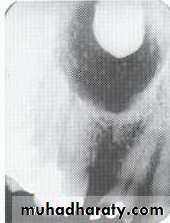

• Aneurysmal Bone Cyst

Large multilocular aneurysmal bone cyst

in the ramus with marked expansion andthe displacement of/8.

It is non-neoplastic ,exaggerated , localized, proliferative lesion of vascular tissue, containing giant cells.

It’s a variation of the central giant cell granuloma , can be diagnosed only by histological examination